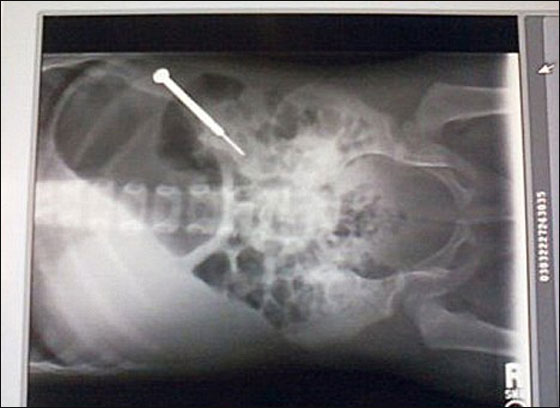

نجت الطفلة شيليا مارتينيز (عامين) من ولاية كولورادو في الولايات المتحدة، بأعجوبة، بعدما ابتلعت مفك براغي. بحيث اقتادها والداها على عجل الى المستشفى، بعدما لاحظوا بانها ليست على ما يرام، وعندما التقطت لها صورة أشعة، ظهر مفك براغي خاص للجيب طوله ثلاثة أنش ونصف في معدتها.

عمل الجراحون حوالي الساعة حتى تمكنوا من اخراج المفك من امعاء الطفلة. ويقول والدا شيليا بأنها تبلي بلاء حسنا، لكن لم يعلموا بعد من اين أتت بهذه الأداة.